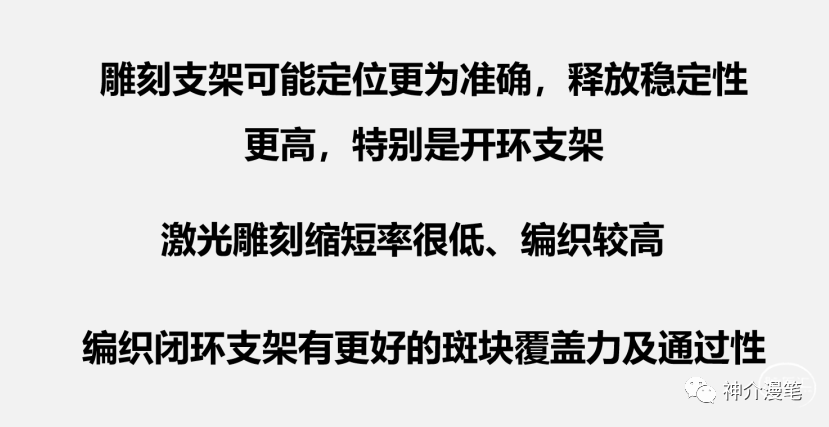

第二个概念:编织支架与雕刻支架。

编织支架:金属丝由机器或手工编制而成,

编织支架在不同管腔内会拉伸,并有释放后短缩现象。雕刻支架:金属圆筒由激光镂空雕刻形成,雕刻支架长度基本稳定,拉伸或短缩的现象极为少见。从结构特点上我们能知道,开环支架全部是雕刻支架,闭环则可能是雕刻也可能是编织。看过我这篇小豆腐块的同志,千万不要再从你们嘴里出现编织开环支架这个词了。下面第一个图,编织闭环支架,第二图为激光雕刻开环支架。

闭环支架更大的优势来源于更密更为紧凑的网孔设计,对于提高局部金属覆盖率,保护斑块脱落,特别是溃疡斑块,软斑块等有其独特的优势。此外对于串联病变,闭环支架具备更好的二次通过性,内壁更为光滑,很少出现导管通过困难等问题。因此对于对于串联病变,夹层修复,编织闭环更具优势。

不同支架具有自己独特的特点,清楚地认识到各自的优缺点,才能更为精准的去选择,扬长避短,发挥最大的治疗效果。OK,接下来就简单分开介绍目前市场上的几大主流颈动脉支架,还是那句话,没有任何利益导向,纯学术探讨,而且更多的是个人理解,所以有不认同的,大家开诚布公的讨论,千万不要拍我的黑砖。